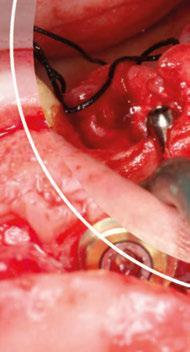

Figura 3. Intervención quirúrgica del caso clínico 1. a) situación clínica basal; b) colgajo de acceso apical vestibular y medición del defecto; c) posicionamiento ideal del injerto de tejido conectivo autólogo; d) sutura del injerto de tejido conectivo autólogo al colgajo a través del acceso apical vestibular.

Figura 4. Intervención quirúrgica del caso clínico 1. a) posición del injerto suturado a través del colgajo de acceso apical vestibular; b) utilización de aloinjerto particulado (OraGRAFT® Aloinjerto Cortical Particulado MIX 70% Mineralizado / 30% Desmineralizado) para rellenar el interior del defecto y cubrir la dehiscencia ósea; c) cobertura de la dehiscencia ósea con el aloinjerto particulado; d) customización de la lámina de cortical acorde a las características del defecto (Lámina de cortical desmineralizada Cortiflex® Salugraft Dental).

Se realiza una incisión biselada hacia coronal a espesor total en forma de parábola cóncava a apical en la mucosa labial con una hoja de bisturí no 10 alejada del fondo de vestíbulo actual. Es necesario destacar que la línea de incisión que estamos realizando se convertirá en el nuevo fondo de vestíbulo al final del procedimiento. El bisturí debe estar orientado a 45o al eje apico-coronal de los dientes. Además, la extensión mesio-distal de la incisión será acorde al número de recesiones adyacentes a tratar, debiendo extendernos idealmente un diente más a cada lado.

Una vez preparado el lecho receptor, dada la existencia de una situación combinada de recesión gingival y una dehiscencia ósea vestibular con pérdida de inserción interproximal, se opta por la utilización combinada de un injerto de tejido conectivo autólogo tuberositario, un sustituto de origen alogénico (Lámina de cortical desmineralizada Cortiflex® Salugraft Dental) que se fija mediante dos chinchetas a ambos lados, cubriendo un injerto óseo de origen alogénico particulado (OraGRAFT® Aloinjerto Cortical Particulado MIX 70% Mineralizado / 30% Desmineralizado). Primero se suturó el injerto de tejido conectivo autólogo al colgajo, después se colocaron las partículas

de injerto óseo y, posteriormente, se fijó la lámina cortical.

Por último, se sutura la línea de incisión a fondo de vestíbulo dando puntos anclados al periostio, permitiendo, con escasos puntos de sutura, cerrar el acceso realizado y dejando la mucosa labial cicatrizando por segunda intención.

Estos puntos se dan atravesando con la sutura el colgajo en dirección corono-apical y, posteriormente, atravesando el periostio en perpendicular en dirección mesio-distal.